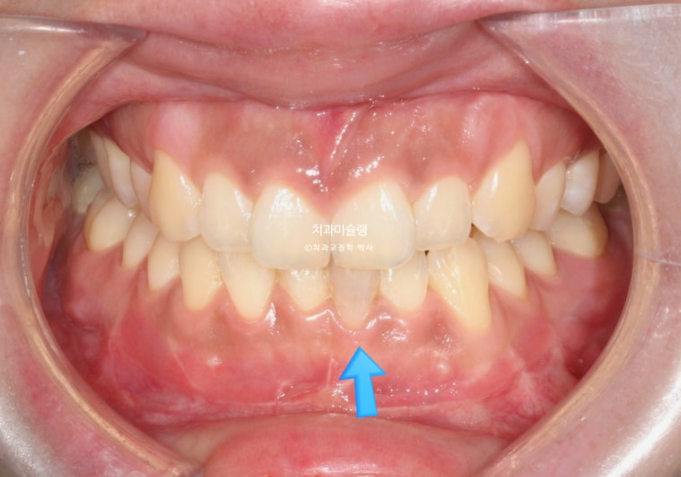

선수술 후 한달간의 회복기를 거쳐 25년 1월 본원에 내원했을 때의 교합 상태입니다.

25.01

아래 앞니 하나에 변색이 보입니다.

수술 직후 일시적으로 신경이 죽는 경우가 있으며 다시 돌아오기도 하니 일단 지켜봅니다.

앞니 두 개는 나비치아 돌출이며

어금니 교합이 떠있습니다.

앞니에 배열이 삐뚤합니다.

이 정도의 상태라면 14개 장치 안에서 해결이 가능합니다.

즉 인비절라인 라이트로도 충분합니다.